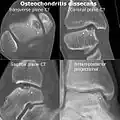

-

CT scan and projectional radiography of a case of osteochondritis dissecans of parts of the superior-medial talus. -

Sagittal MRI: Linear low T1 signal at the articular surfaces of the lateral aspects of the medial condyle of the femur confirms the presence of OCD. -